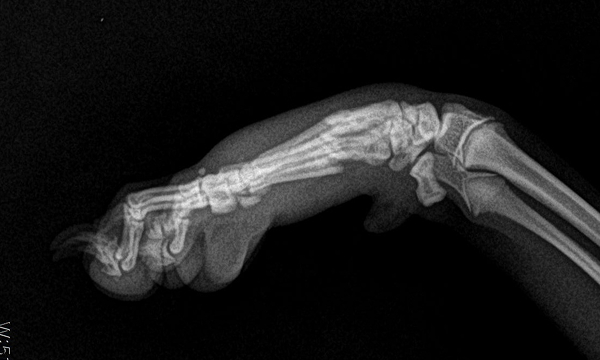

수술케이스 ② 보*강아지 - 요척골 단순골절

수술케이스 2 before BEFORE

수술케이스 2 after AFTER